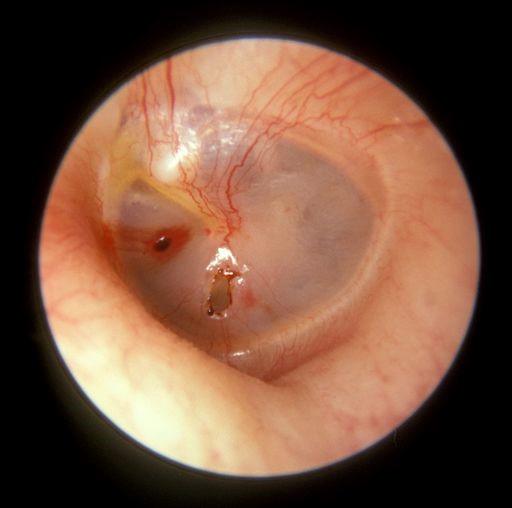

Perforación de la membrana timpánica

Por Michael Hawke MD (obra de Won), CC BY 4.0vía Wikimedia Commons